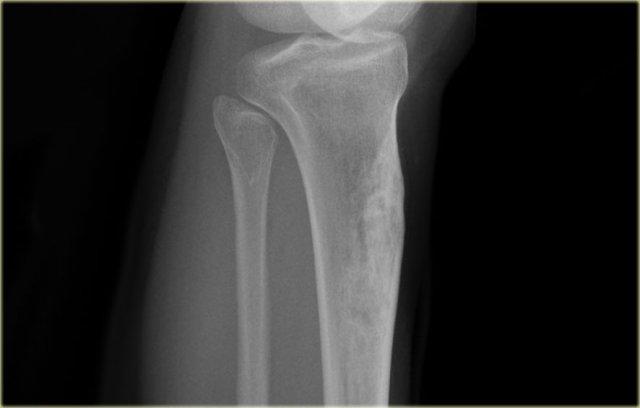

Đây là hình ảnh của một bệnh nhân bị viêm tủy xương mạn tính.

Ở trung tâm có một vùng tiêu xương không rõ ranh giới.

Phần lớn tổn thương bao gồm xơ cứng phản ứng.